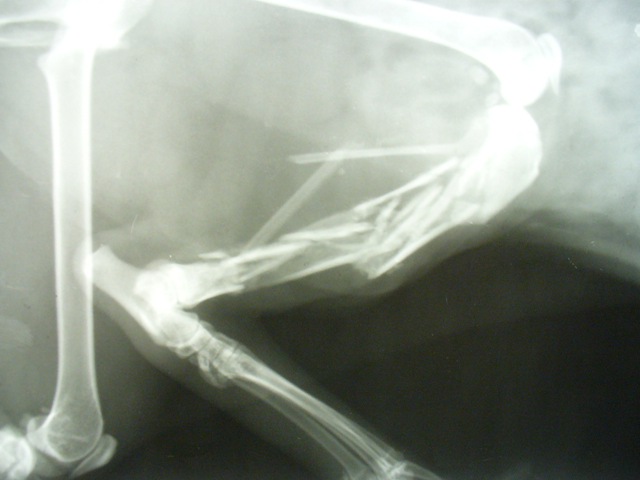

Итак, вы упали на тротуаре, в результате чего, кроме полученного испуга, получили еще и перелом кисти, например.

Во-вторых, получаем в травмпункте справочку, в которой указано время и место вашего обращения и, разумеется, вид полученной травмы. Более того, следует иметь в виду и необходимость в дальнейшем представить в суд больничный лист с указанием диагноза и времени (периода) утраты трудоспособности.